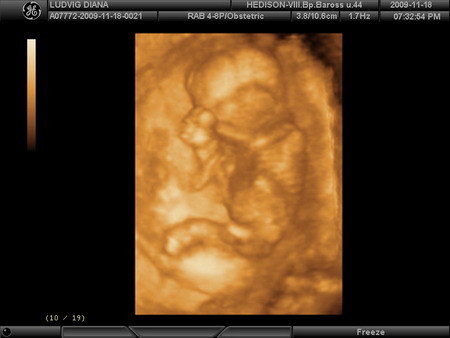

Kis Tündérkénk 27 hetesen és 1 naposan:

Kép Kép Kép Kép